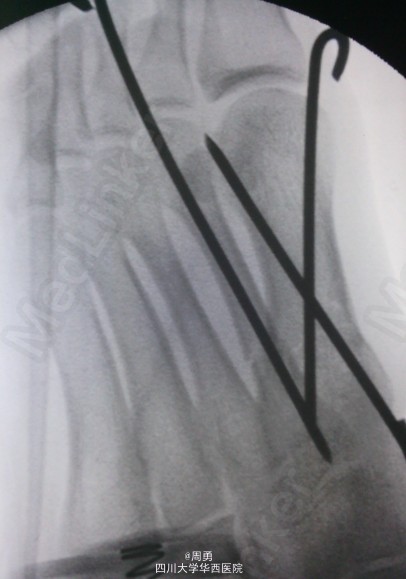

左足第1,2跖骨中近1/3骨折闭合复位克氏针内固定术

此手术为做博士住院总时所做,复位比较满意,价格便宜,效果确实。病例简介:33Y,M,诊断:左足第1,2跖骨中近1/3骨折;处理:行闭合复位克氏针内固定术。